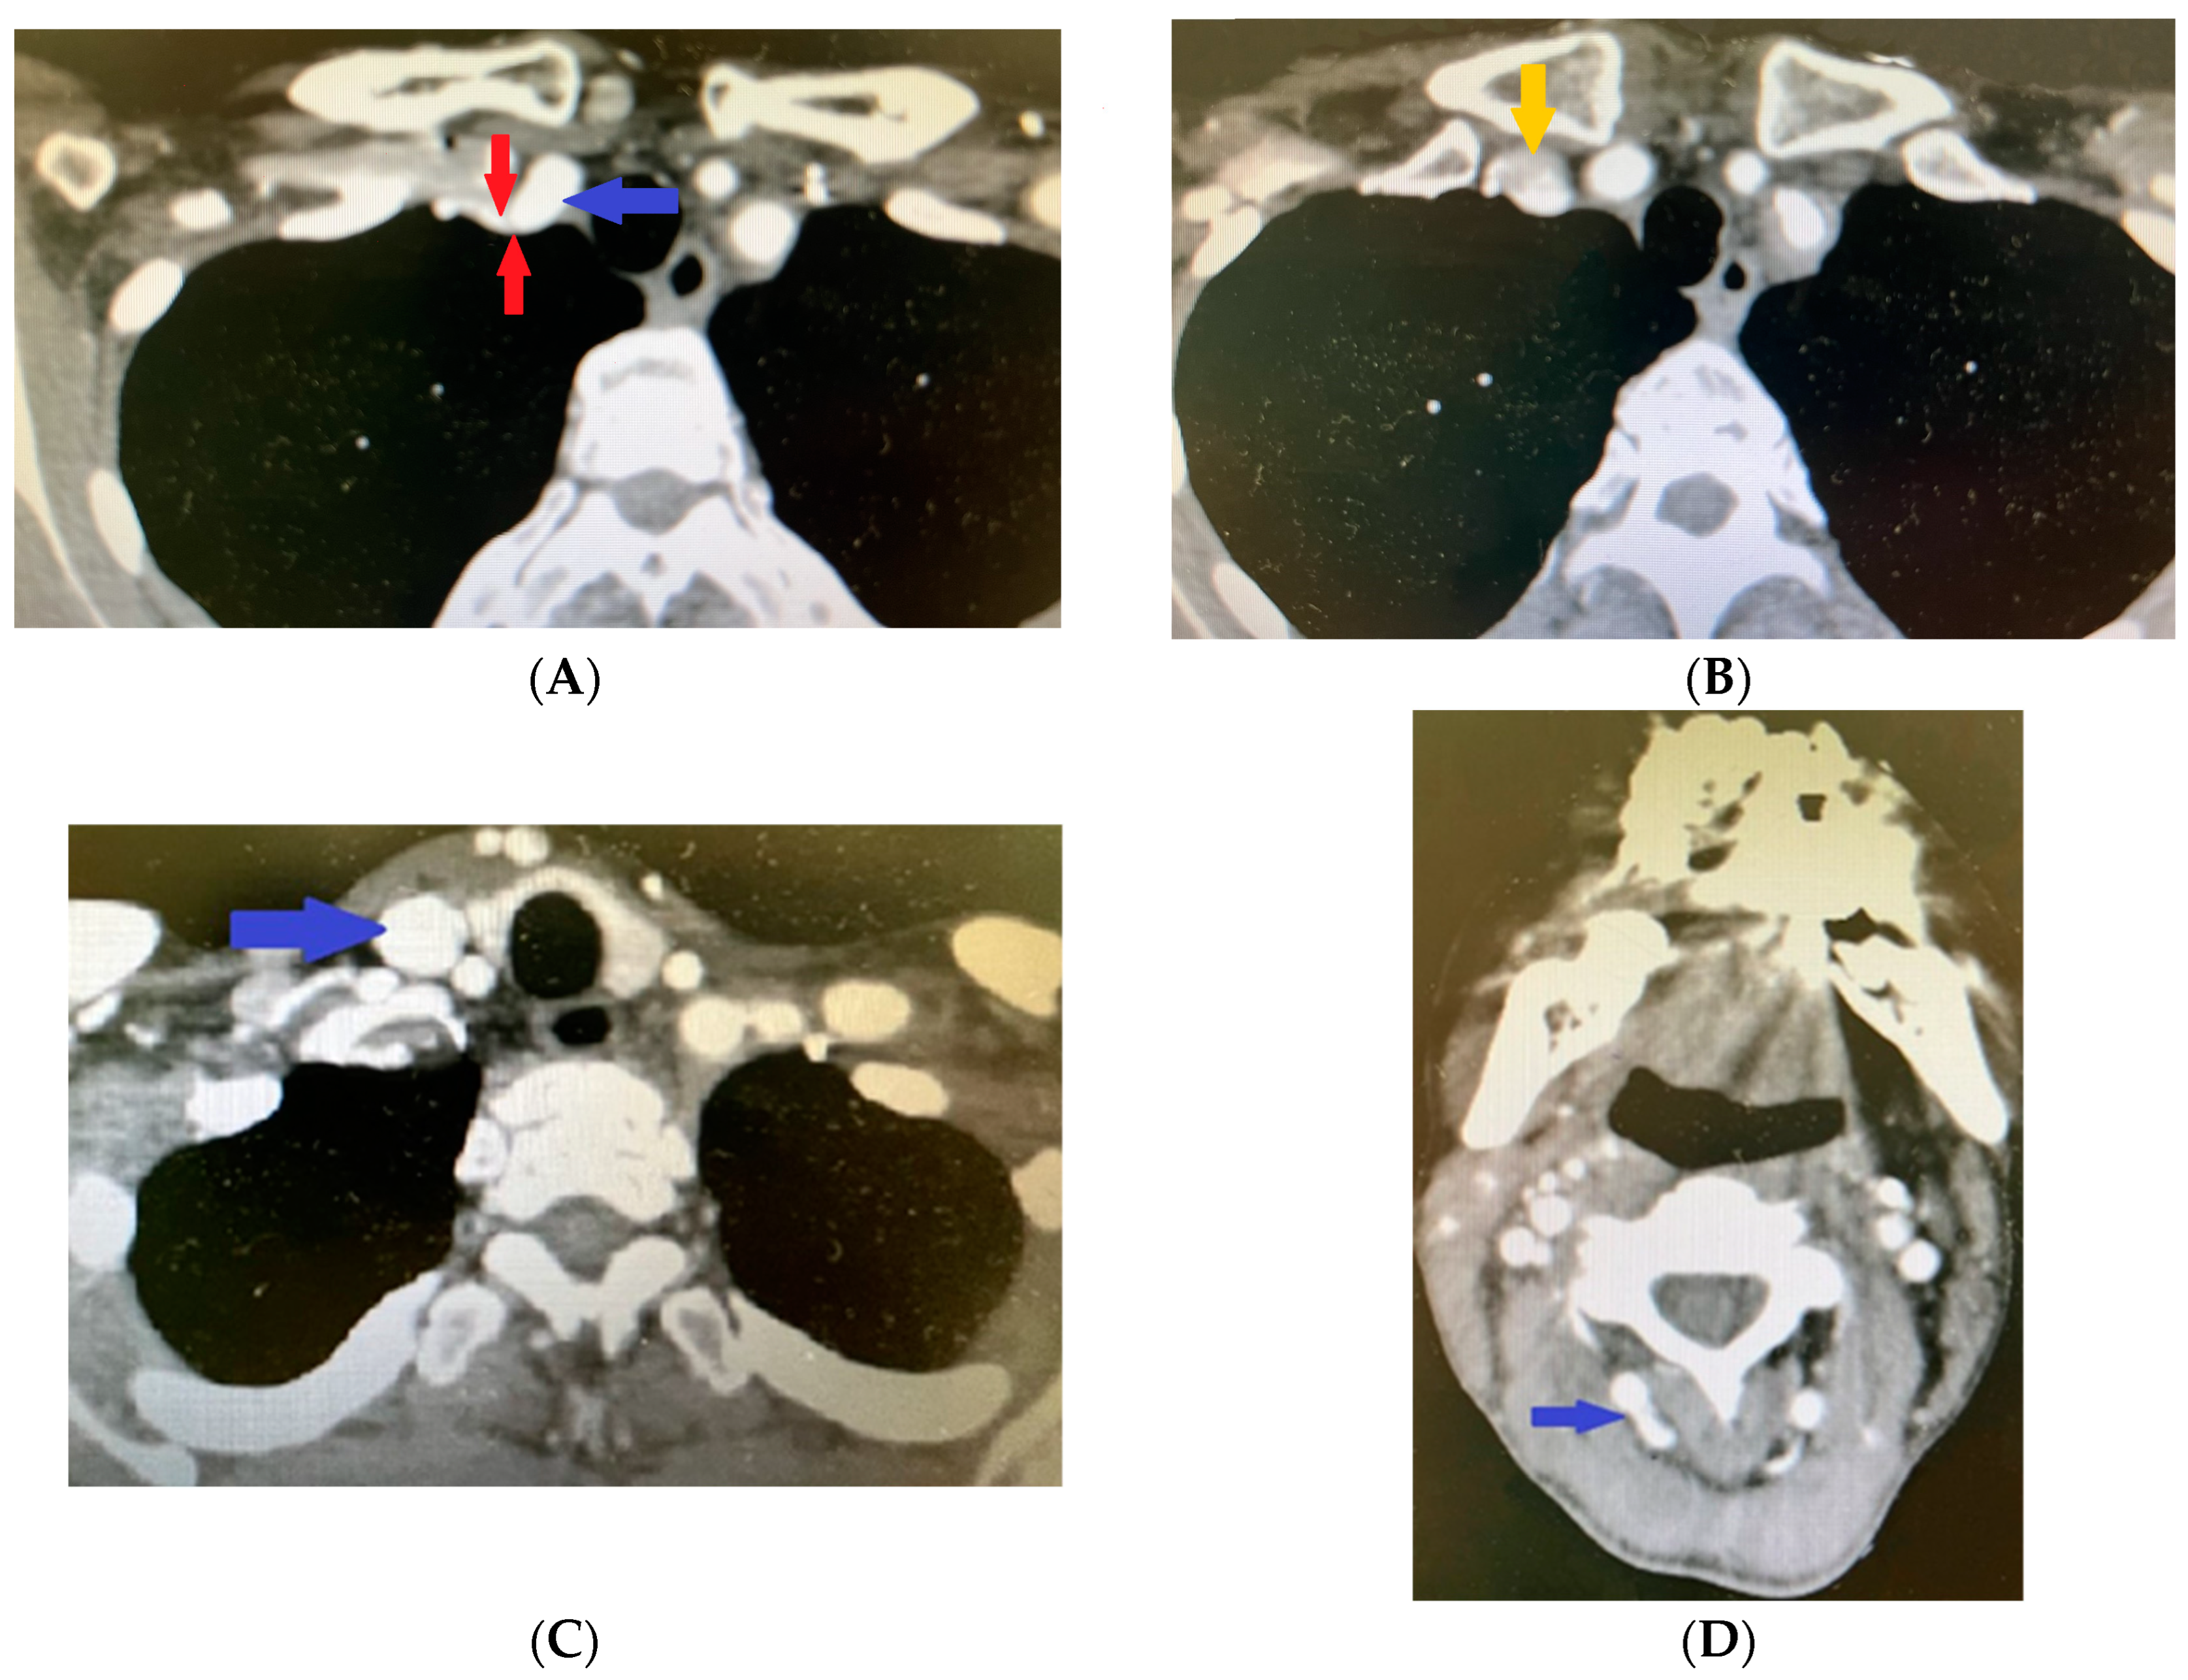

Significant pathological deviations were also present in the left extracranial vessels; the left subclavian artery had parietal thrombosis and a fusiform aneurysmal dilatation of 68 mm after the ostium, with maximum axial dimensions of 50 by 31 mm (Figure 6A).

Figure 6.

Contrast-enhanced computed tomography revealing (A) dilated left subclavian artery (blue arrow) and parietal thrombosis in the left subclavian artery (yellow arrows). Contrast-enhanced computed tomography revealing (B) aneurismal dilatation of left internal carotid artery. Contrast-enhanced computed tomography revealing (C) fusiform dilatation of left vertebral artery.

The CT scan revealed calcium plaques in the bifurcation region of the common carotid artery, but no discernible stenosis. Calcium plaques also impacted the internal carotid artery, which resulted in stenosis at the pars petrosa–pars cavernosa transition and intracranial aneurysmal dilation (Figure 6B).

Immediately after the ostium, an 11.5 to 12.5 mm aneurysmal dilatation was seen in the external carotid artery. Pathological fusiform dilatation was also seen in the vertebral artery (Figure 6C).